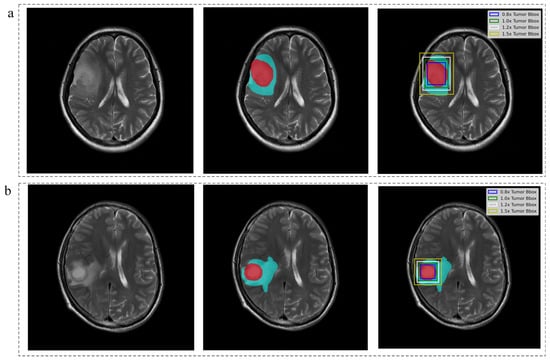

| Image Inputs | Description | |

|---|---|---|

| i | Tumor slice | the whole slices contained the tumor mask |

| ii | Tumor mask | the tumor region alone by setting all outside tumor pixels as zero |

| iii | Tumor mask + Edema | The joint region that contained both tumor region and the edema region by setting all outside pixels as zero |

| iv | 0.8× Tumor Bbox | downscaled the bounding box of tumor mask by 0.8 |

| v | 1.0× Tumor Bbox | bounding box of tumor mask |

| vi | 1.2× Tumor Bbox | enlarged the bounding box of tumor mask by 1.2 times |

| vii | 1.5× Tumor Bbox | enlarged the bounding box of tumor mask by 1.5 times |